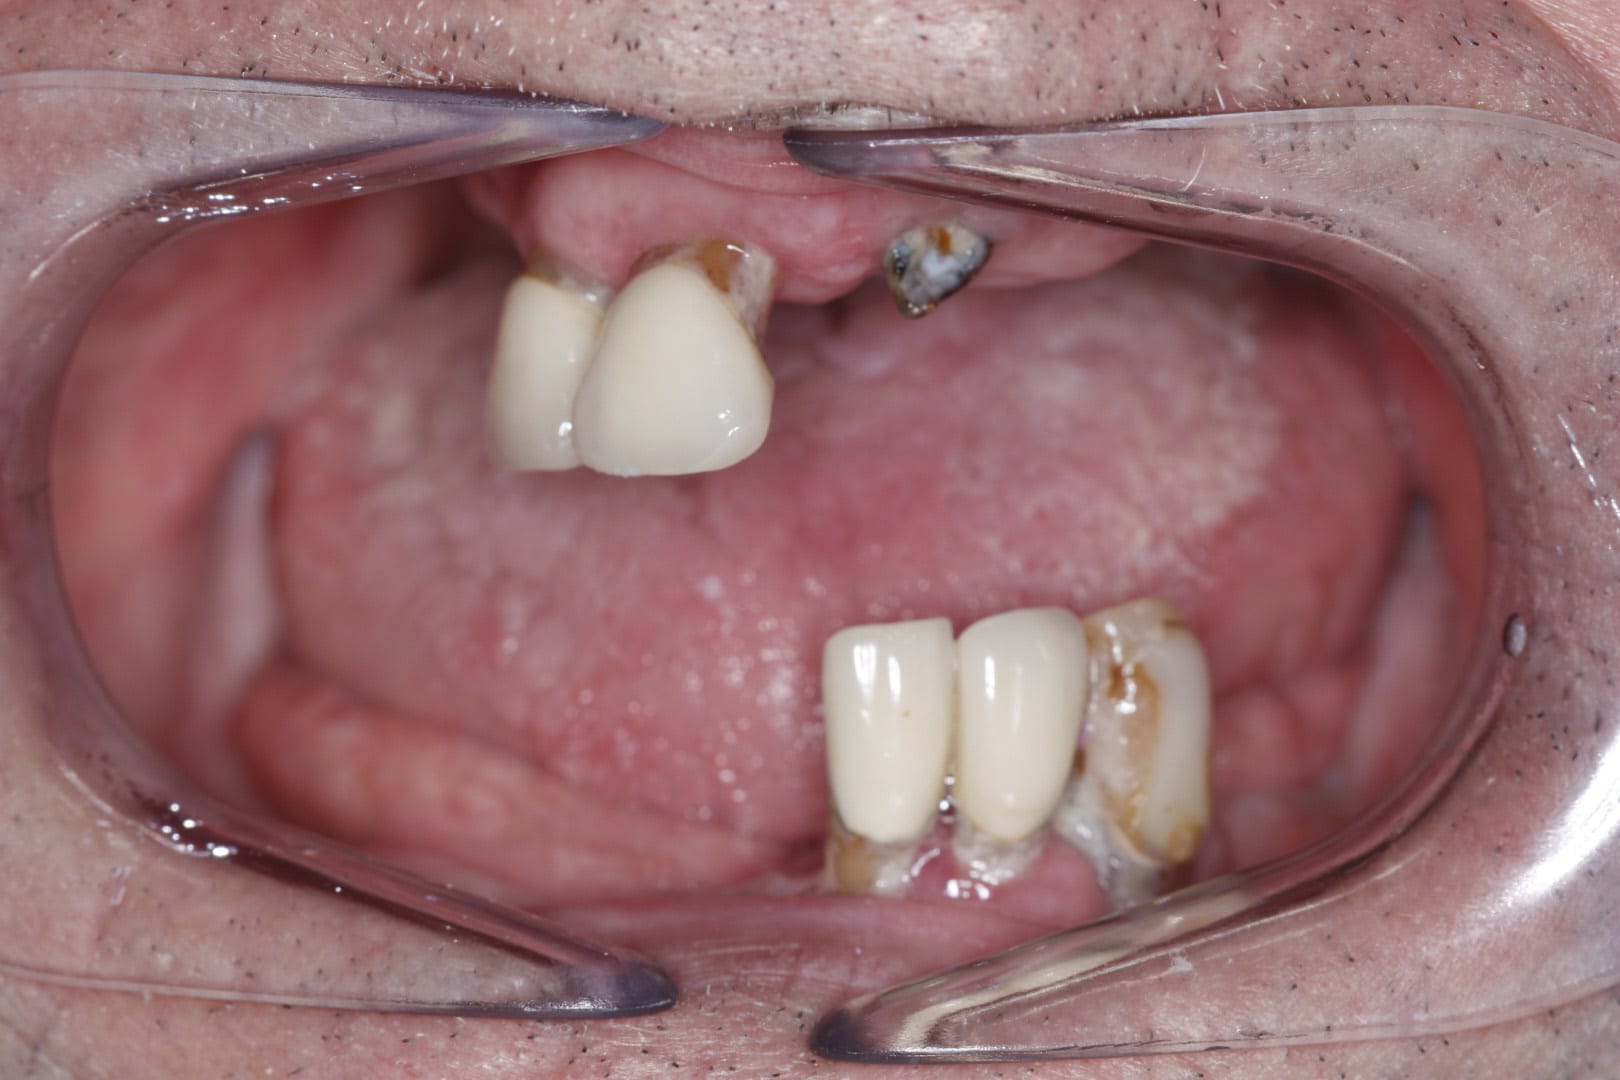

Our incredible implant results

Our dental implant results speak for themselves! We’re so proud of the smile transformations we’ve helped our patients achieve with strong and secure dental implants and our patient-focused care. Ready for your new smile? Get in touch today to find out more, or book your appointment online!